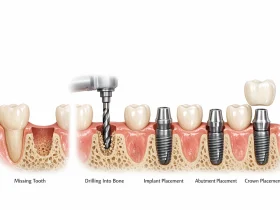

برای موفقیت ایمپلنت، لازم است پایه فلزی آن به طور کامل با استخوان فک جوش بخورد. این فرایند که به آن «اُسواینتگریشن» گفته میشود، نقش مهمی در ثبات ایمپلنت دارد. در برخی موارد این اتصال بهدرستی انجام نمیشود و ایمپلنت نمیتواند به طور پایدار در استخوان قرار بگیرد.

عدم جوش خوردن ایمپلنت با استخوان